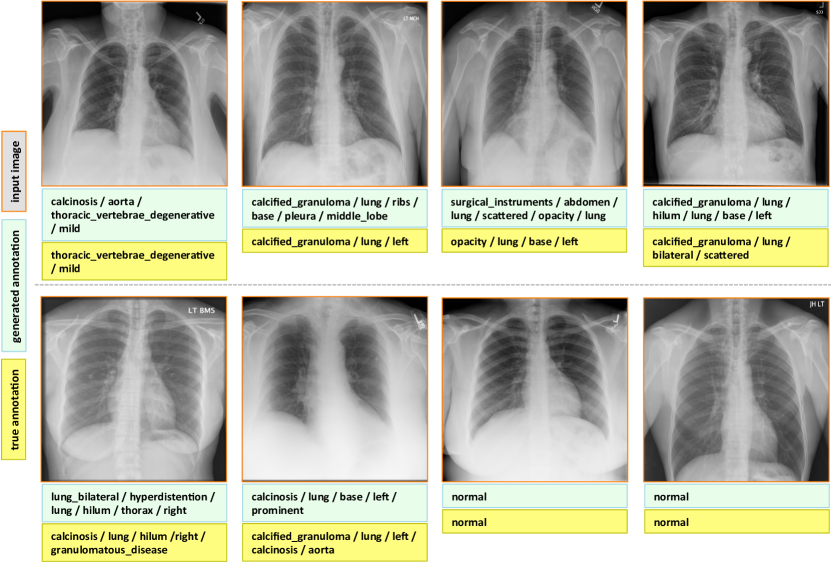

7.1 Evaluation

The final evaluated BLEU scores are provided in Table 5. We achieve better overall BLEU scores than those in Table 4 before using the joint image/text context. It is noticeable that higher BLEU-N () scores are achieved compared to Table 4, indicating that more comprehensive image contexts are taken into account for the CNN/RNN training. Also, slightly better BLEU scores are obtained using GRU on average and higher BLEU-1 scores are acquired using LSTM, although the comparison is empirical. Examples of generated annotations on the chest x-ray images are shown in Figure 6. These are generated using the GRU model, and more examples can be found in the supplementary material.

Appendix C More Annotation Generation Examples

More annotation generation examples are provided in Figures 10 and 11. Overall, the system generates promising results on predicting disease (labels) and its context (attributes) in the images. However, rare disease cases are more difficult to detect. For example, the cases pulmonary_atelectasis, spondylosis, and density (Figure 10), as well as foreign_bodies, atherosclerosis, costophrenic_angle, deformity (Figure 11) are much rarer in the data than calcified_granuloma, cardiomegaly, and all the frequent cases listed in Table 1 of the main paper.

Furthermore, the (left or right) location of the disease cannot be identified in a lateral view (obtained by scanning the patient from the side), as shown in Figure 11. Since our dataset contains a limited number of disease cases, we treat each x-ray image and report as a sample, and do not account for different views.